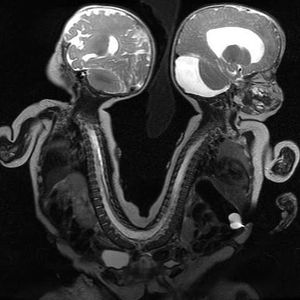

MR image of conjoined twins.